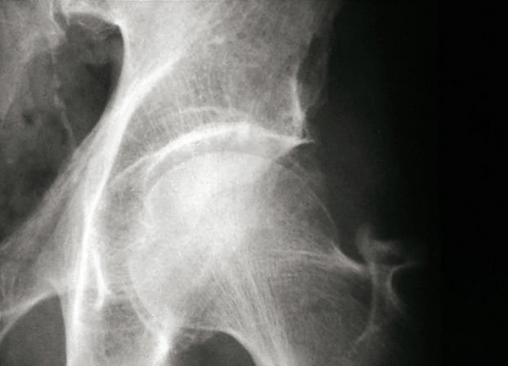

Radiographie hanche (face). Chondrocalcinose articulaire : liseré calcique du cartilage de la tête fémorale. Extrait de : Chalès G, Guggenbuhl P. Arthropathie microcristalline. Rev Prat 2013;63(5):709-20.